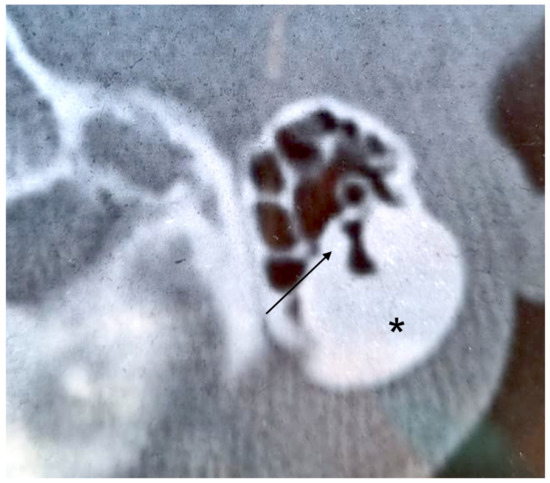

3.1. Case 1